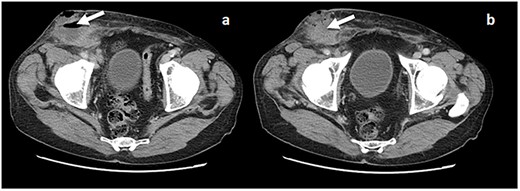

Computerized tomography (CT-scan) revealed an apparent right recurrent inguinal hernia with satellite regional lymph nodes of 15 mm and an 8-cm fluid collection and air in the subcutaneous tissue (Fig. 1a and b).

(a and b) CT scan with evidence of a fluid collection in the right inguinal area (arrow) and an apparent recurrent hernia.